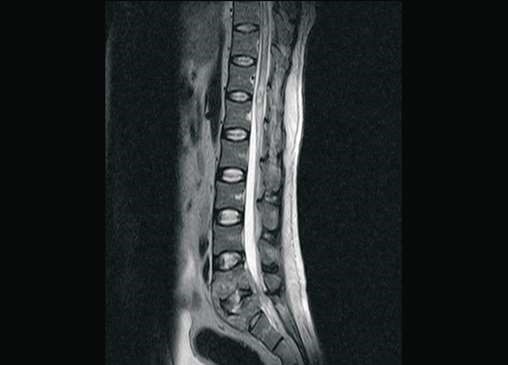

MRI: spinal epidural abscess